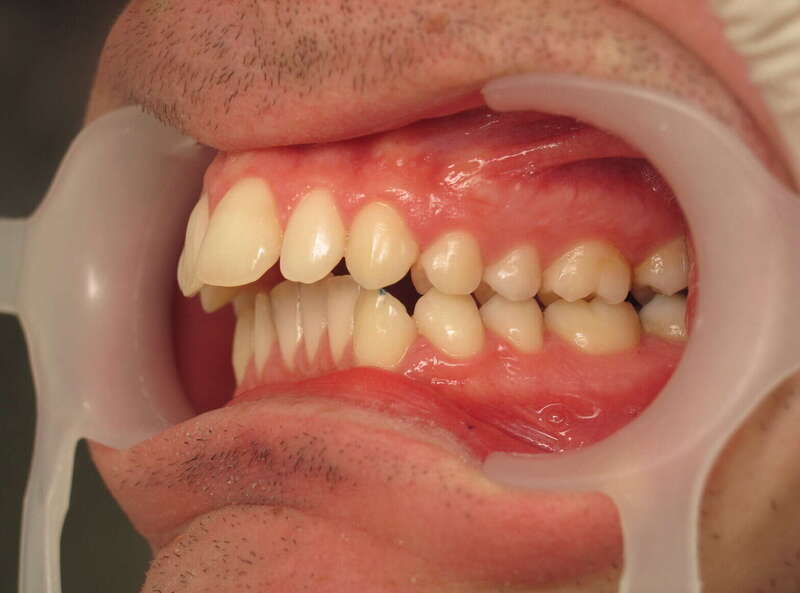

Cas n°1 traité par aligneurs - adolescent

Ce cas d’une adolescente illustre la correction d'une Classe II avec supraclusion par aligneurs. La stratégie thérapeutique a reposé sur une distalisation séquentielle de l'arcade supérieure. Ce mouvement précis a permis de reculer les dents maxillaires étape par étape pour annuler le surplomb (overjet) sans extractions.

• Correction fonctionnelle : Retour à un engrènement de Classe I stable et correction du recouvrement vertical.

• Esthétique restaurée : Harmonisation globale du sourire et du profil.

• Approche moderne : Un traitement discret, confortable et hautement prévisible.

Le résultat final montre une occlusion saine et un sourire parfaitement aligné, garantissant une santé dentaire et articulaire optimale pour l'avenir.

Avant

Après